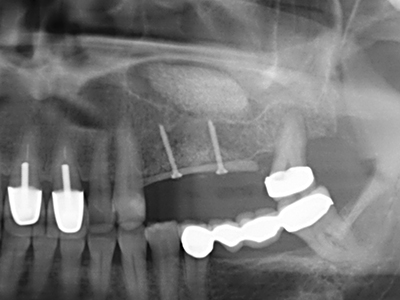

La preparación de la ventana lateral en la elevación del suelo del seno maxilar representa un enorme reto, sobre todo para profesionales de la implantalogía que tienen poca experiencia en técnicas quirúrgicas. Retirar la cobertura ósea del seno maxilar sin provocar daños en la membrana de Schneider es tan solo una parte de la operación; tras crear un acceso suficiente, es preciso movilizar con cuidado la mucosa del seno maxilar a fin de dejar espacio para el material o los implantes que vayan a incorporarse. En esta aplicación la cirugía piezoeléctrica resulta útil en dos sentidos: por un lado, el uso de insertos diamantados permite realizar una retirada selectiva del hueso y, si se actúa con cuidado, la membrana permanece intacta, y por otro lado, las frecuencias de ultrasonidos favorecen también un desprendimiento sin problemas de la membrana, pues se transfieren al espacio comprendido entre la mucosa y el suelo del seno maxilar gracias al uso de piezas romas especiales (Cassetta, Ricci et al. 2012, Pereira, Gealh et al. 2014) (Rickert, Vissink et al. 2013). De este modo, no es de extrañar los trabajos publicados en la actualidad sobre la técnica de elevación del suelo del seno maxilar mediante la técnica de Caldwell-Luc con instrumentos piezoeléctricos (Wallace, Tarnow et al. 2012).

En la extracción de bloques óseos la piezocirugía también presenta ventajas adicionales: Además de la alta precisión en la osteotomía que ya se ha descrito antes, se ha comprobado que el uso de los delgados insertos de sierra resulta especialmente cuidadosas con el hueso. Frente a esto, sobre todo cuando se usan las fresas de Lindemann, cabe esperar pérdidas en la extracción significativamente más altas debido al mayor grosor de la parte frontal del cabezal (Lakshmiganthan, Gokulanathan et al. 2012). La separación basal que se necesita en particular en los injertos de bloque extraídos de forma retromolar se ve facilitada mediante sierras perpendiculares especialmente previstas a tal fin, lo que permite considerar que la cirugía piezoeléctrica es un procedimiento preciso y seguro para la obtención de bloques de hueso en el área retromolar (Happe 2007) (fig. 1-12).